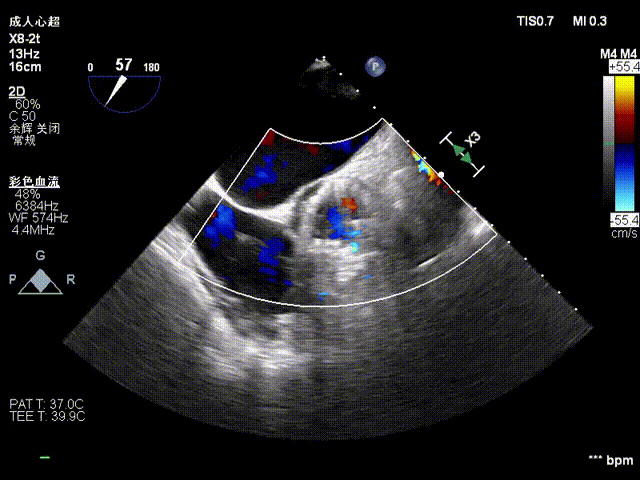

术前超声

术后超声

在DSA与超声引导下,手术团队高效精准地完成了瓣膜的定位、释放与功能评估。手术过程顺利,夹持件入窦与定位一气呵成,三枚夹持件的释放与锚定位置与术前评估完全一致,器械用时仅6min左右。患者主动脉瓣重度反流纠正,术后无反流、无瓣周漏。术后心脏彩超显示人工生物瓣启闭良好,平均跨瓣压差3mmHg,流速正常,舒张压从30mmHg提升至70mmHg。